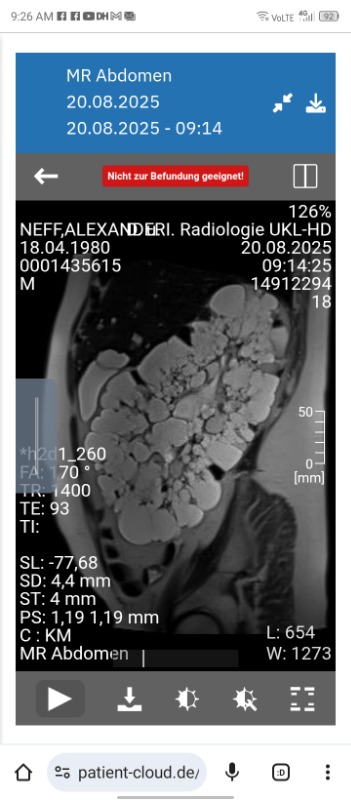

Suche Klink für beidseitige Nephrektomie meiner Zystennieren 20 Feb 2026 17:43 #528997